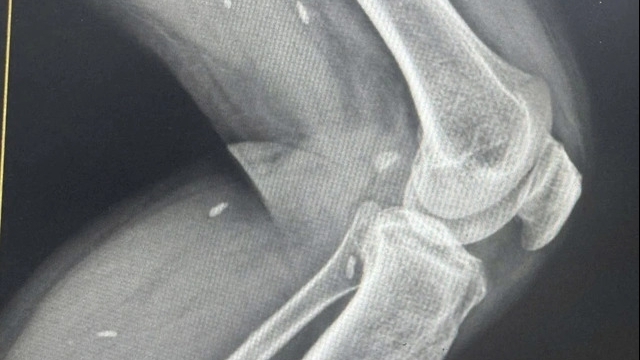

![]() |

| Hình ảnh bé B.A sau phẫu thuật ghép gan (đã được cho phép của người giám hộ). Ảnh: Lê Hiếu |